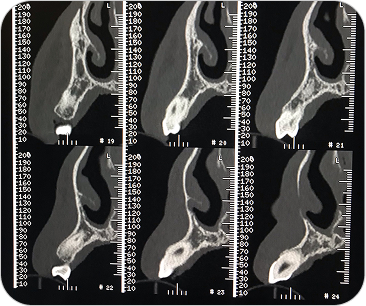

Dental Scan (Tomografía 3D Dental)

El Dental Scan o Tomografía Computada de Haz Cónico (CBCT) es un estudio especializado que brinda imágenes tridimensionales de alta resolución del sistema dentomaxilofacial. Es fundamental en odontología avanzada, permitiendo planificaciones precisas y diagnósticos más seguros.

La tomografía dental (CBCT) es un estudio esencial en odontología avanzada, que permite ver el maxilar, mandíbula y piezas dentales en 3D para diagnósticos y tratamientos más seguros.

UTILIDAD

- Planificación de implantes dentales.

- Evaluación de muelas del juicio y piezas retenidas.

Diagnóstico de quistes, lesiones óseas o problemas articulares.

VENTAJAS

- Imágenes 3D de alta resolución.

- Baja radiación.

- Ideal para odontología, ortodoncia y cirugía maxilofacial

¿PARA QUÉ SE UTILIZA?

- Planificación de implantes dentales con medición exacta del hueso.

- Evaluación de muelas del juicio o dientes incluidos.

- Estudio de quistes, tumores o lesiones óseas de mandíbula y maxilar.

- Diagnóstico de patología articular (ATM).

- Detección de fracturas, reabsorciones o infecciones profundas.

- Cirugías ortognáticas y procedimientos maxilofaciales complejos.

¿POR QUÉ ES UN ESTUDIO DESTACADO?

- Imágenes en 3D reales y de alta definición.

- Mucho más preciso que una radiografía panorámica tradicional.

- Estudio rápido, cómodo y con baja dosis de radiación.

Dental Scan (Tomografía 3D Dental)

El Dental Scan o Tomografía Computada de Haz Cónico (CBCT) es un estudio especializado que brinda imágenes tridimensionales de alta resolución del sistema dentomaxilofacial. Es fundamental en odontología avanzada, permitiendo planificaciones precisas y diagnósticos más seguros.

La tomografía dental (CBCT) es un estudio esencial en odontología avanzada, que permite ver el maxilar, mandíbula y piezas dentales en 3D para diagnósticos y tratamientos más seguros.

UTILIDAD

- Planificación de implantes dentales.

- Evaluación de muelas del juicio y piezas retenidas.

Diagnóstico de quistes, lesiones óseas o problemas articulares.

VENTAJAS

- Imágenes 3D de alta resolución.

- Baja radiación.

- Ideal para odontología, ortodoncia y cirugía maxilofacial

¿PARA QUÉ SE UTILIZA?

- Planificación de implantes dentales con medición exacta del hueso.

- Evaluación de muelas del juicio o dientes incluidos.

- Estudio de quistes, tumores o lesiones óseas de mandíbula y maxilar.

- Diagnóstico de patología articular (ATM).

- Detección de fracturas, reabsorciones o infecciones profundas.

- Cirugías ortognáticas y procedimientos maxilofaciales complejos.

¿POR QUÉ ES UN ESTUDIO DESTACADO?

- Imágenes en 3D reales y de alta definición.

- Mucho más preciso que una radiografía panorámica tradicional.

- Estudio rápido, cómodo y con baja dosis de radiación.